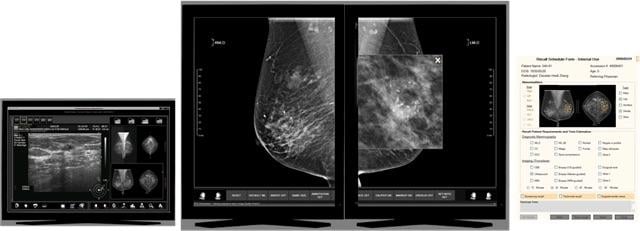

June 12, 2019 — Three Palm Software announced the release of the 1.8.8 version of its breast imaging workstation, WorkstationOne. This release builds on the existing comprehensive support for mammography, with enhancements in several areas. An emphasis of this release is expanded custom display mechanisms for new mammography computer-aided detection (CAD) systems, decision support and breast density reports. This includes customized report display for approximately 20 different vendors (not all of which are available for clinical use yet).

Tomosynthesis CAD from vendors such as iCAD and ScreenPoint, and interactive decision support for ScreenPoint’s Transpara products, are all supported. The system can also automatically extract and display scoring information from the received reports and include that in the user’s reading worklist in order to prioritize reading order. Similarly, breast density information from vendors such as Volpara, Densitas and iCAD is extracted and displayed with the images, and can be used to set the initial state for reported breast density.